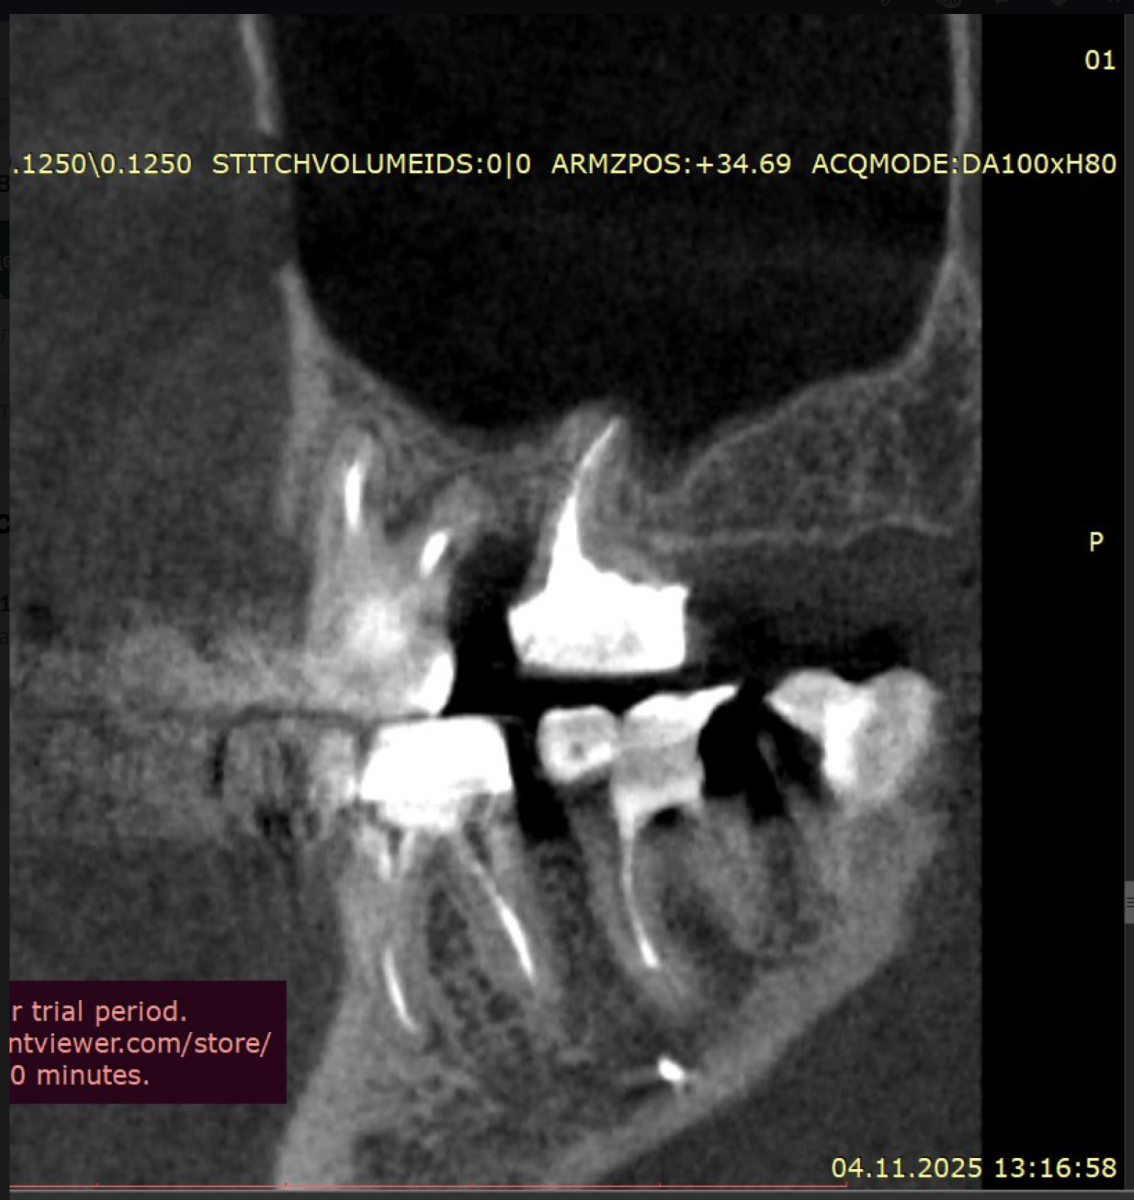

Sergey32132 Опубликовано 5 декабря, 2025 Поделиться Опубликовано 5 декабря, 2025 (изменено) Добрый день. Зубы проблемные с детства очень сильно Полтора-два года назад предварительно удалось спасти не спасаемое, 26 и 27, по крайней мере по нескольких кт перидически, неплохой регресс и заживление костной ткани, даже в области 26 где было большое поражение фуркации, сейчас намного меньше, они не болят уже почти год, до этого очень долго болели даже после качественного лечения и врачи прогнозов не давали конечно же между 24-26 (25 нет уже лет 10) стоит адегизивный бабочка, уже не в самом лучшем состоянии, вернее зубы 24 26 не в очень хорошем, так вот я хотел снять бабочку и одеть на 24-26 металлокерамику, во рту есть несколько металлокерамик единичных, на 3 еще не ставил Есть вариант, и я послушал разных докторов, что можно было бы например 24 просто сделать реставрацию качественно, 26 там без вариантов покрыть коронкой единичной, а 25 имплантат, но я пока избегаю всего так сказать инвазивного, хотя бы еще полтора-два года, с начала 2024 и по середину 2025 болел очень тяжело, Лонг ковидом, это страшное явление которое врагу не пожелаю, возможно даже кто помнит мои темы что я у себя предполагал сепсис, вот именно у меня был он не в виде усталости какой и тд, что чаще всего, а в форме выраженного иммунодефицита + легкого но стойкого системного воспаления , по типу аутоиммунных реакций, в общем не будем вдаваться в эту тему, к тому же она не изучена еще, все только предстоит, спасибо лишь тем докторам-интузиастам, которые просто из спортивного интереса не забросили эту тему и занимаются исследованиями, при разных НИИ, в итоге они меня спасли, помогли определенные противовирусные на длительной основе поставить меня на ноги, что еще раз и том числе мой пример подтверждает вирусный генез Лонга, 1,5 жизни просто выпало у меня Ладно, я далеко ушел уже от темы, я к тому, что более современно наверное считается имплантат и 24 и 26 по отдельности, но повторюсь я боюсь пока лишних инвазивных процедур. Подскажите пожалуйста, каковы минусы моста с металлокерамики на 3 зуба, по каким причинам это считается прошлый век, и какие нюансы меня могут ждать ? Даже если те зубы я рано или поздно потеряю, но даже 3-4 года выиграть еще перед имплантацией, это все равно выигрыш Возможно я думал тот же мост на 3 но из циркония, но тоже не знаю, зубы те хоть и с положительной динамикой но сколько они еще простоят, а цирконий как никак в 2 раза дороже металлокерамики, но если лучше его, тогда рассмотрю Изменено 5 декабря, 2025 пользователем Sergey32132 Ссылка на комментарий